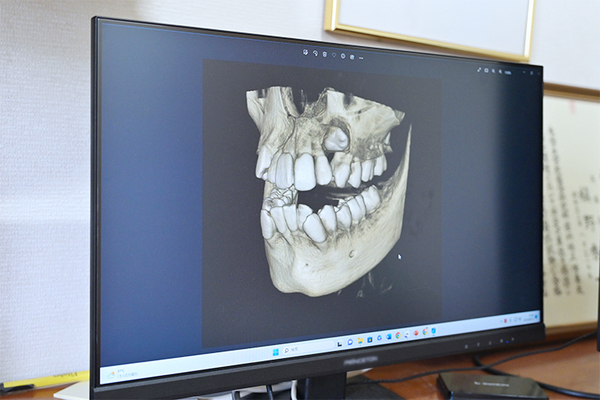

▲最も効率良く矯正治療が行えることが見込める装置を提案している

矯正方法を決める上で最も大切なのが「診断」です。各種エックス線、型採り、口腔内写真、お顔の写真、顎の動き・筋肉の検査などを行い、総合的に診断して決定します。また矯正治療で重要なのが歯の動かし方。めざす動きに対して最も効率良く歯が動くことが見込める装置を考え、提案します。患者さんが希望する矯正方法にももちろん対応しますが、その方に合ってない方法であればお伝えします。各装置のメリット・デメリットを十分にご説明し、ご納得いただいた上で矯正を開始。なお当院では表側・裏側の各ワイヤー矯正、マウスピース型装置を用いた矯正、床矯正など、多種類の矯正方法に対応しており、口腔筋機能療法にも対応しています。

▲患者一人ひとりに応じて、さまざまな対応が可能なワイヤー矯正

ワイヤーを用いた矯正であるエッジワイズ法は1920年代に誕生し、長い年月をかけてノウハウを蓄積してきた矯正方法です。矯正時の歯の動きは、骨の硬さ・根っこの大きさや長さ・噛む力・骨格などにより人それぞれ異なるのですが、歯が動きにくいケースにもさまざまな対応方法があることが最大の強み。また歯の動きに応じて、ワイヤーを調整できるのも利点です。エックス線画像から取得した数値や診断・治療のデータを積み上げており、矯正後の歯の角度や位置といった数値を大切にした矯正がめざせるため、抜歯を必要とする方など中等度以上の難症例では特に多く用いられます。